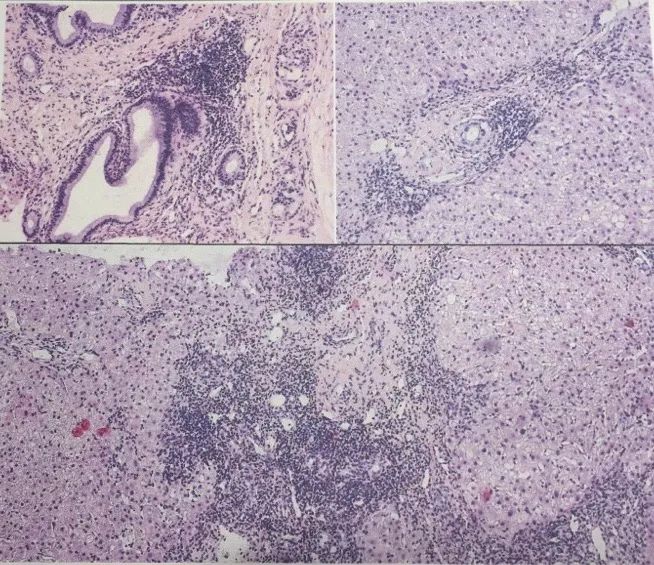

与患者及家属沟通行肝活检病理检查送北京中日友好医院,病理检查如下:

PSC病理特点: 胆管周围洋葱皮样纤维化。

AIH病理特点: 以界面型肝炎、淋巴-浆细胞浸润、肝细胞玫瑰花环排列、淋巴细胞传入为特点。

DILI病理特点: 以炎性细胞浸润、凋亡小体、界面炎、肝细胞点状坏死、肝细胞水样变性为特点,与AIH共同特点有界面炎、门管炎和局灶坏死。